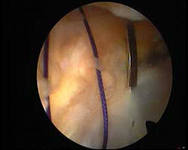

Еще одно достоинство — отсутствие заметного рубца, который неизбежно образуется после обычной операции, требующей больших разрезов. При артроскопии делают небольшие проколы (длиной в несколько миллиметров), которые быстро заживают, почти не оставляя следов (рис 1).